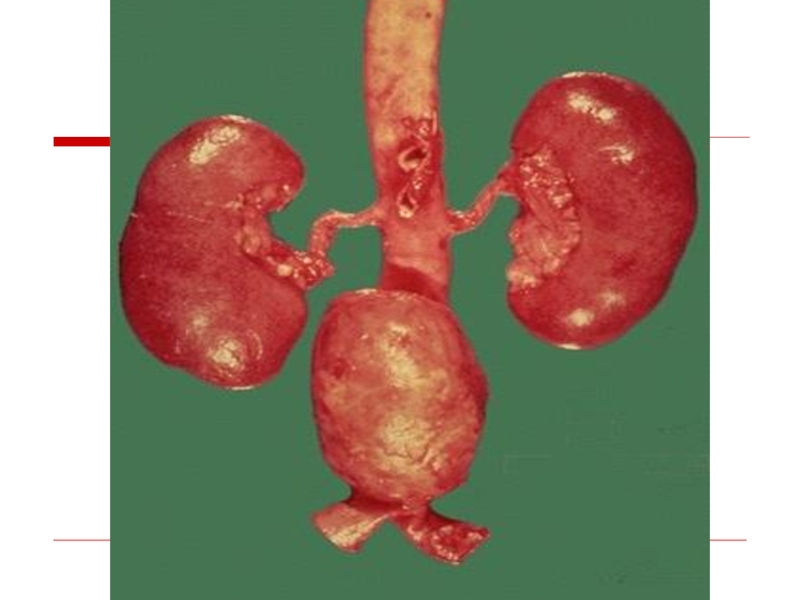

Atherosclerosis of renal arteries leads to the development of atherosclerotic

macrotuberous kidney

Atherosclerosis of renal arteries leads to the development of atherosclerotic  macrotuberous kidney

Слайд 36Atherosclerotic nephrosclerosis

Atherosclerotic nephrosclerosis